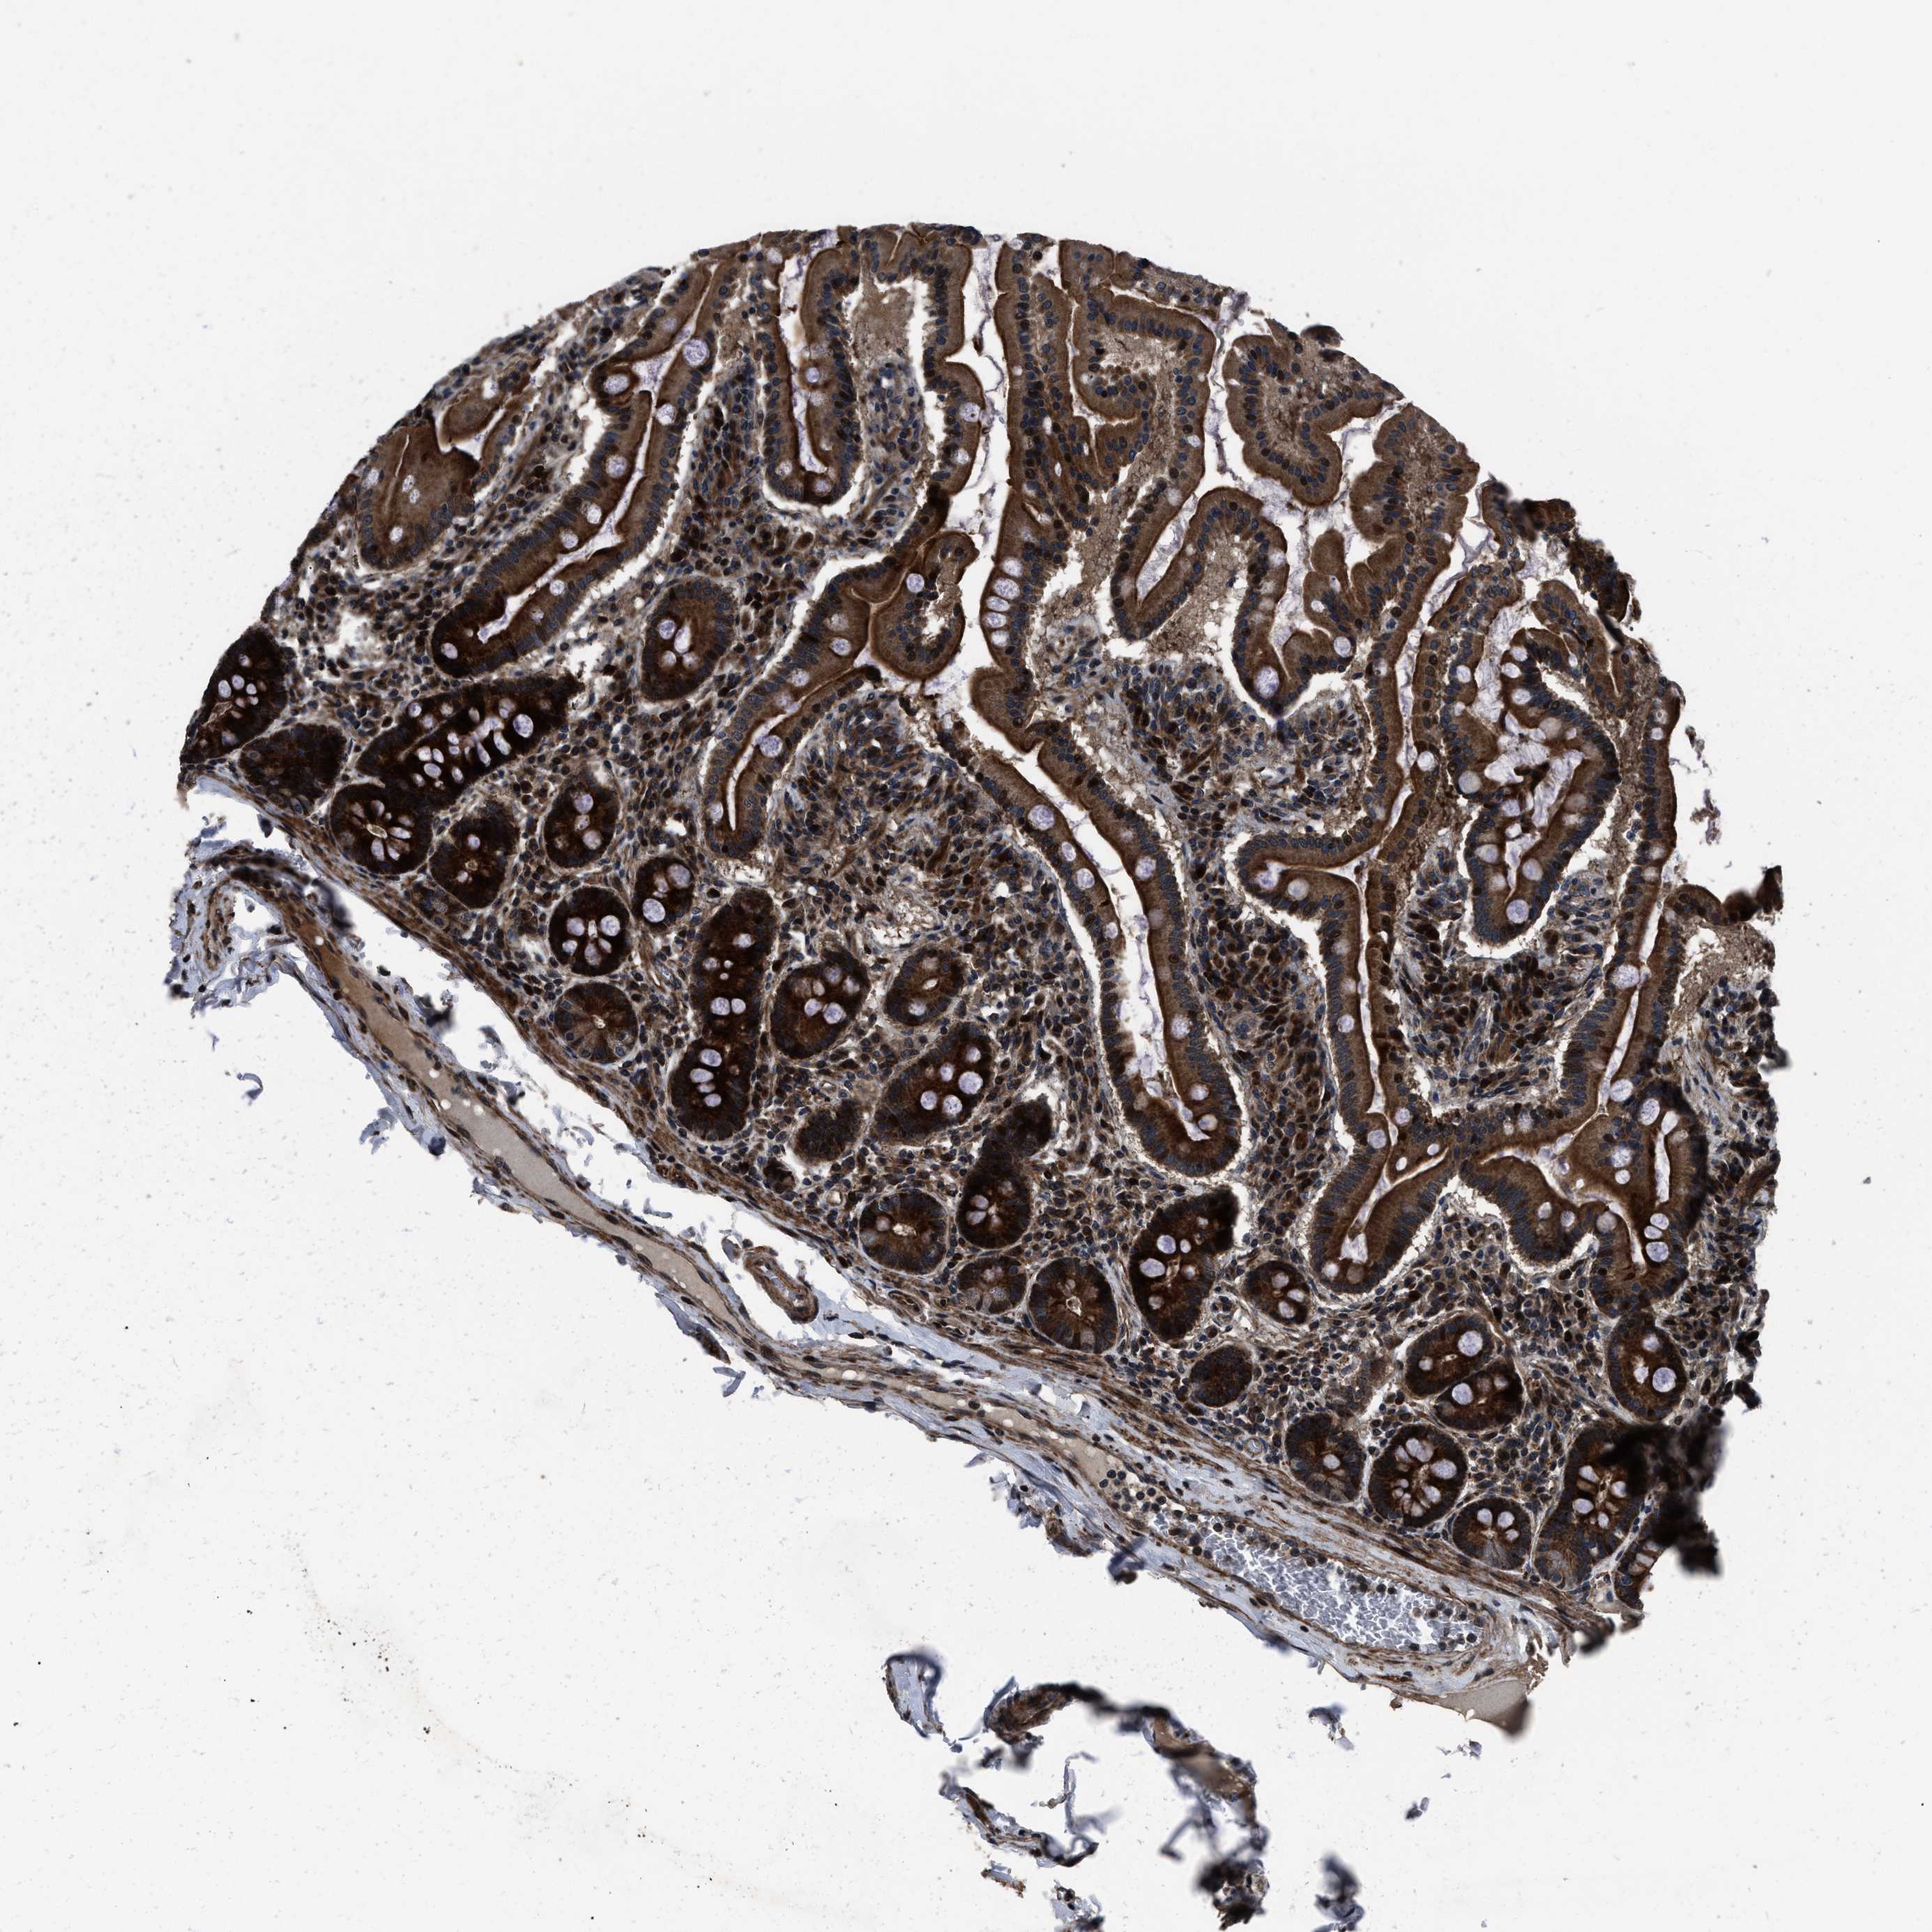

NSD3